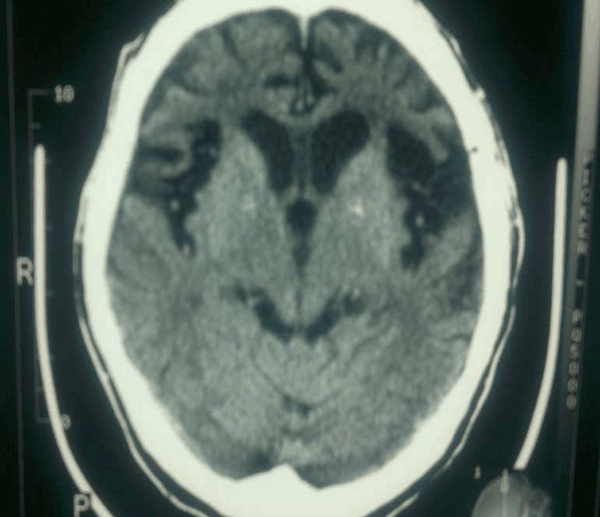

Patient's full blood count, renal functions, thyroid functions, liver functions and routine urine examinations were normal. He tested negative for HIV, Hepatitis B, Hepatitis C, venereal disease research laboratory test (VDRL), and treponema palladium hemagglutination test (TPHA). His serum electrolytes were normal. Based on the history and clinical presentation, a diagnosis of dementia with Herpes simplex of left thigh was considered. Computed tomography scan of the brain showed atrophy of frontal and temporal areas of the brain. (Figure 1) (Figure 2) (Figure 3) (Figure 4)

Figure 3: Bifrontotemporal atrophy and prominent sylvian fissures. Frontal horns of the ventricles are dilated.

Macroscopic examination of the brain of a patient with FTLD typically shows symmetrical focal atrophy of the frontal lobes, temporal lobes. Microscopic examination of the cerebral cortex in most forms of FTLD, shows microvacuolation and neuronal loss. On staining for deposits in neurons, abnormal tau protein aggregates (46%) and ubiquitin-positive inclusions (29%) were found.[6] Our patient had frontal and temporal lobe atrophy on CT scan. The exact etiology and pathophysiology of frontotemporal dementia is incompletely understood but recent studies suggest that genetics plays an important role in disease causation. [7] This is supported by the fact that about 50% of patients with frontotemporal dementia (FTD) report a positive family history. [7]